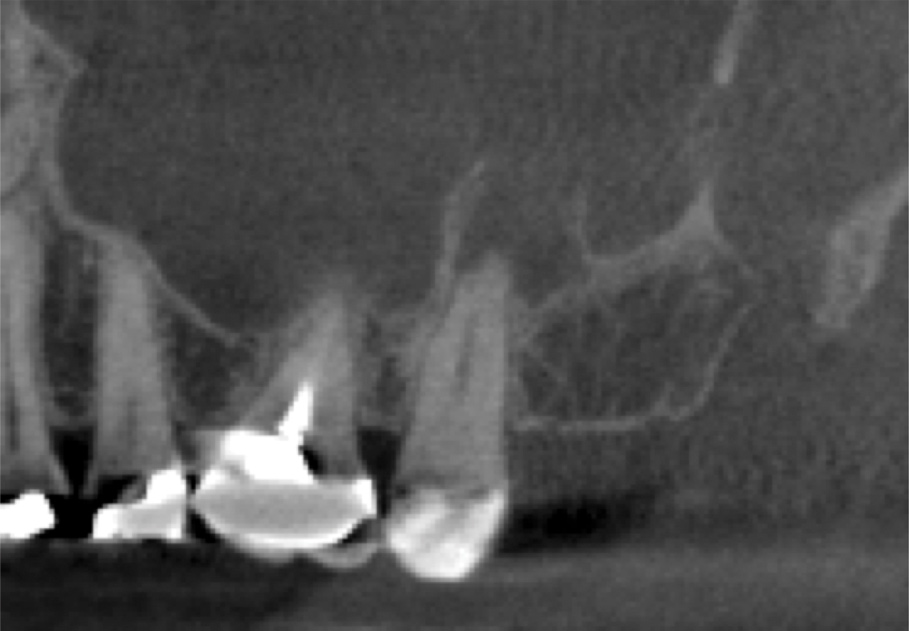

A 58-year-old female patient presented to the office with a 3-month history of acute sinusitis, during which six courses of antibiotics, including penicillin, cephalosporin, and quinolone drugs, had failed to resolve her symptoms. She had been referred for endodontic evaluation by her ENT specialist after imaging revealed endodontic pathosis of tooth No. 2. On initial presentation, tooth No. 2 was nonvital (ie, nonresponsive to cold or electric pulp testing), tested positive to percussion and palpation, and was without swelling, sinus tracts, or periodontal defects. The preoperative CBCT scan revealed apical pathosis on the buccal and palatal roots of tooth No. 2, complete opacification of the right maxillary and ethmoid sinuses, and disruption of the lateral/posterior antral wall posterior to the zygomaticomaxillary buttress (Figure 6). Root canal therapy was initiated. Upon access, black staining of the pulp tissue was observed, indicating necrosis. Pulpal debridement was performed, and calcium hydroxide was utilized as an intracanal medication. Several weeks after pulpal debridement, the patient's sinus symptoms improved, but incompletely. Tooth No. 2 was obturated, and the patient was referred to an ENT specialist for further care.

Three months after NSRCT and one month after FESS, she returned to her endodontist for a follow-up appointment. She reported experiencing only minor sinus pressure, which she believed to be attributed to seasonal allergies. Upon examination, no swelling, mobility, or sinus tracts were noted, and tooth No. 2 was not tender to percussion or palpation. CBCT imaging revealed both clearing of the sinus and initial healing of the apical pathosis (Figure 7 and Figure 8). Continued follow-up appointments were recommended.

This case demonstrates a typical presentation of MSEO, in which an apical radiolucency obliterated the cortical bone of the sinus, causing a direct communication between the two structures. NSRCT was used to treat the dental etiology and following resolution of the apical pathosis, resulted in the restoration of the cortical boundary between the root apex and maxillary sinus. The severity of the pathosis necessitated significant sinus treatment to achieve resolution, including dental, medical, and surgical interventions.

(6.) Preoperative CBCT image showing periapical pathosis of tooth No. 2 in communication with the sinus.

Figure 6

(7.) Postoperative CBCT images taken 3 months after NSRCT (ie, 6 weeks after sinus surgery), showing sinus clearing and reduction in the size of the PAO lesion.

Figure 7

(8.) Postoperative CBCT images taken 3 months after NSRCT (ie, 6 weeks after sinus surgery), showing sinus clearing and reduction in the size of the PAO lesion.

Figure 8